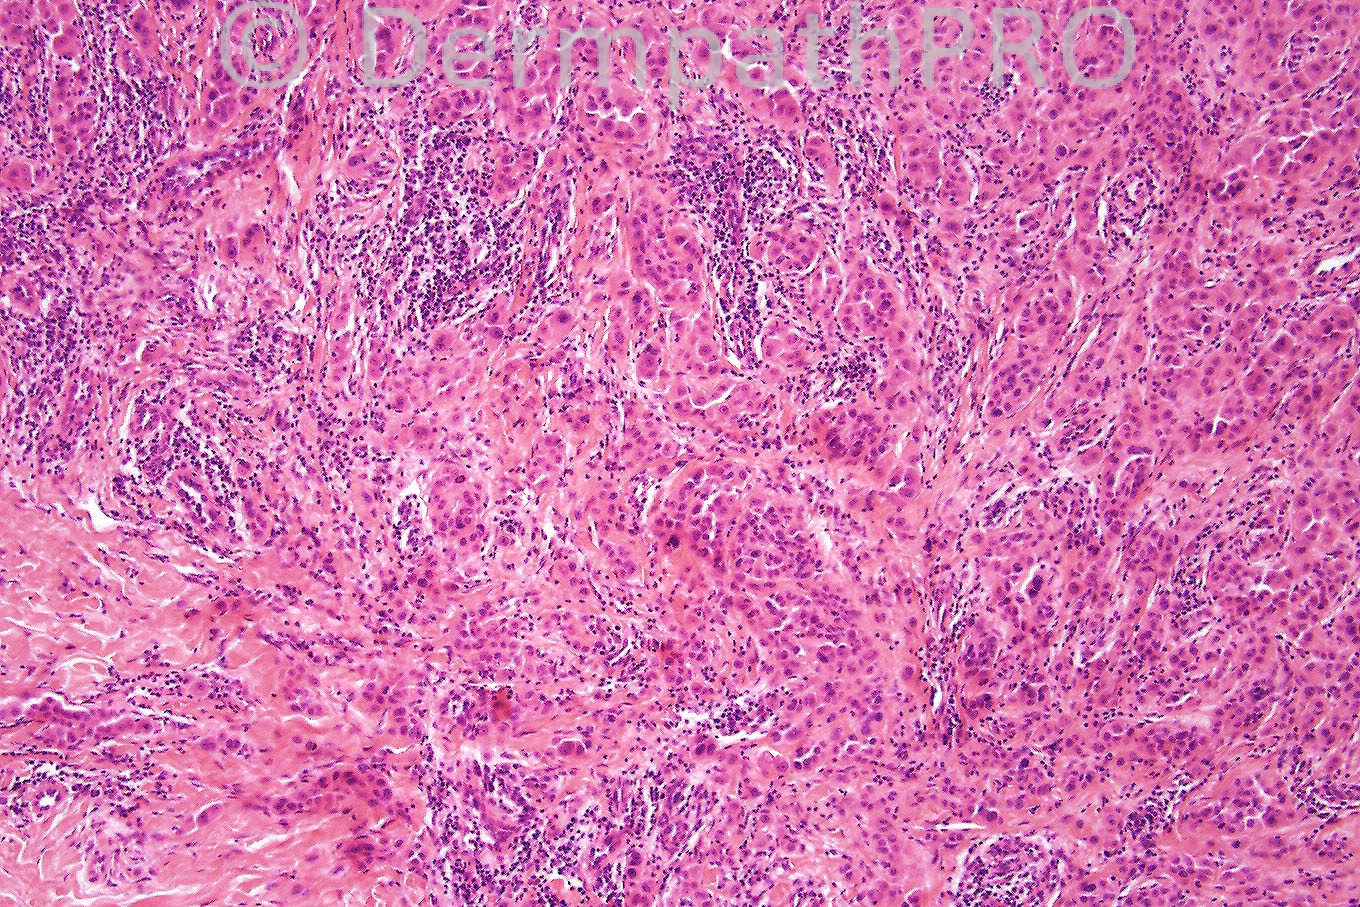

Female 18 years, red nodule on back with surrounding pale halo.